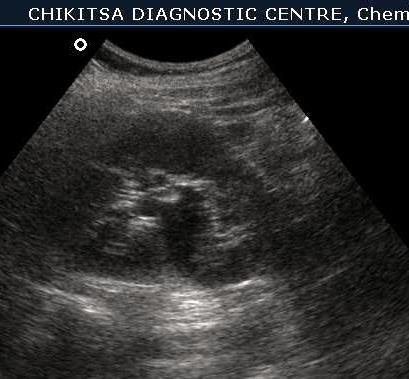

July-Aug 2012 :

Lesion in the wall of the urinary bladder has increased in size. Calcific areas are noted. Urinary bladder malignancy ( confirmed by histopathology), possibly following schistosomiasis.